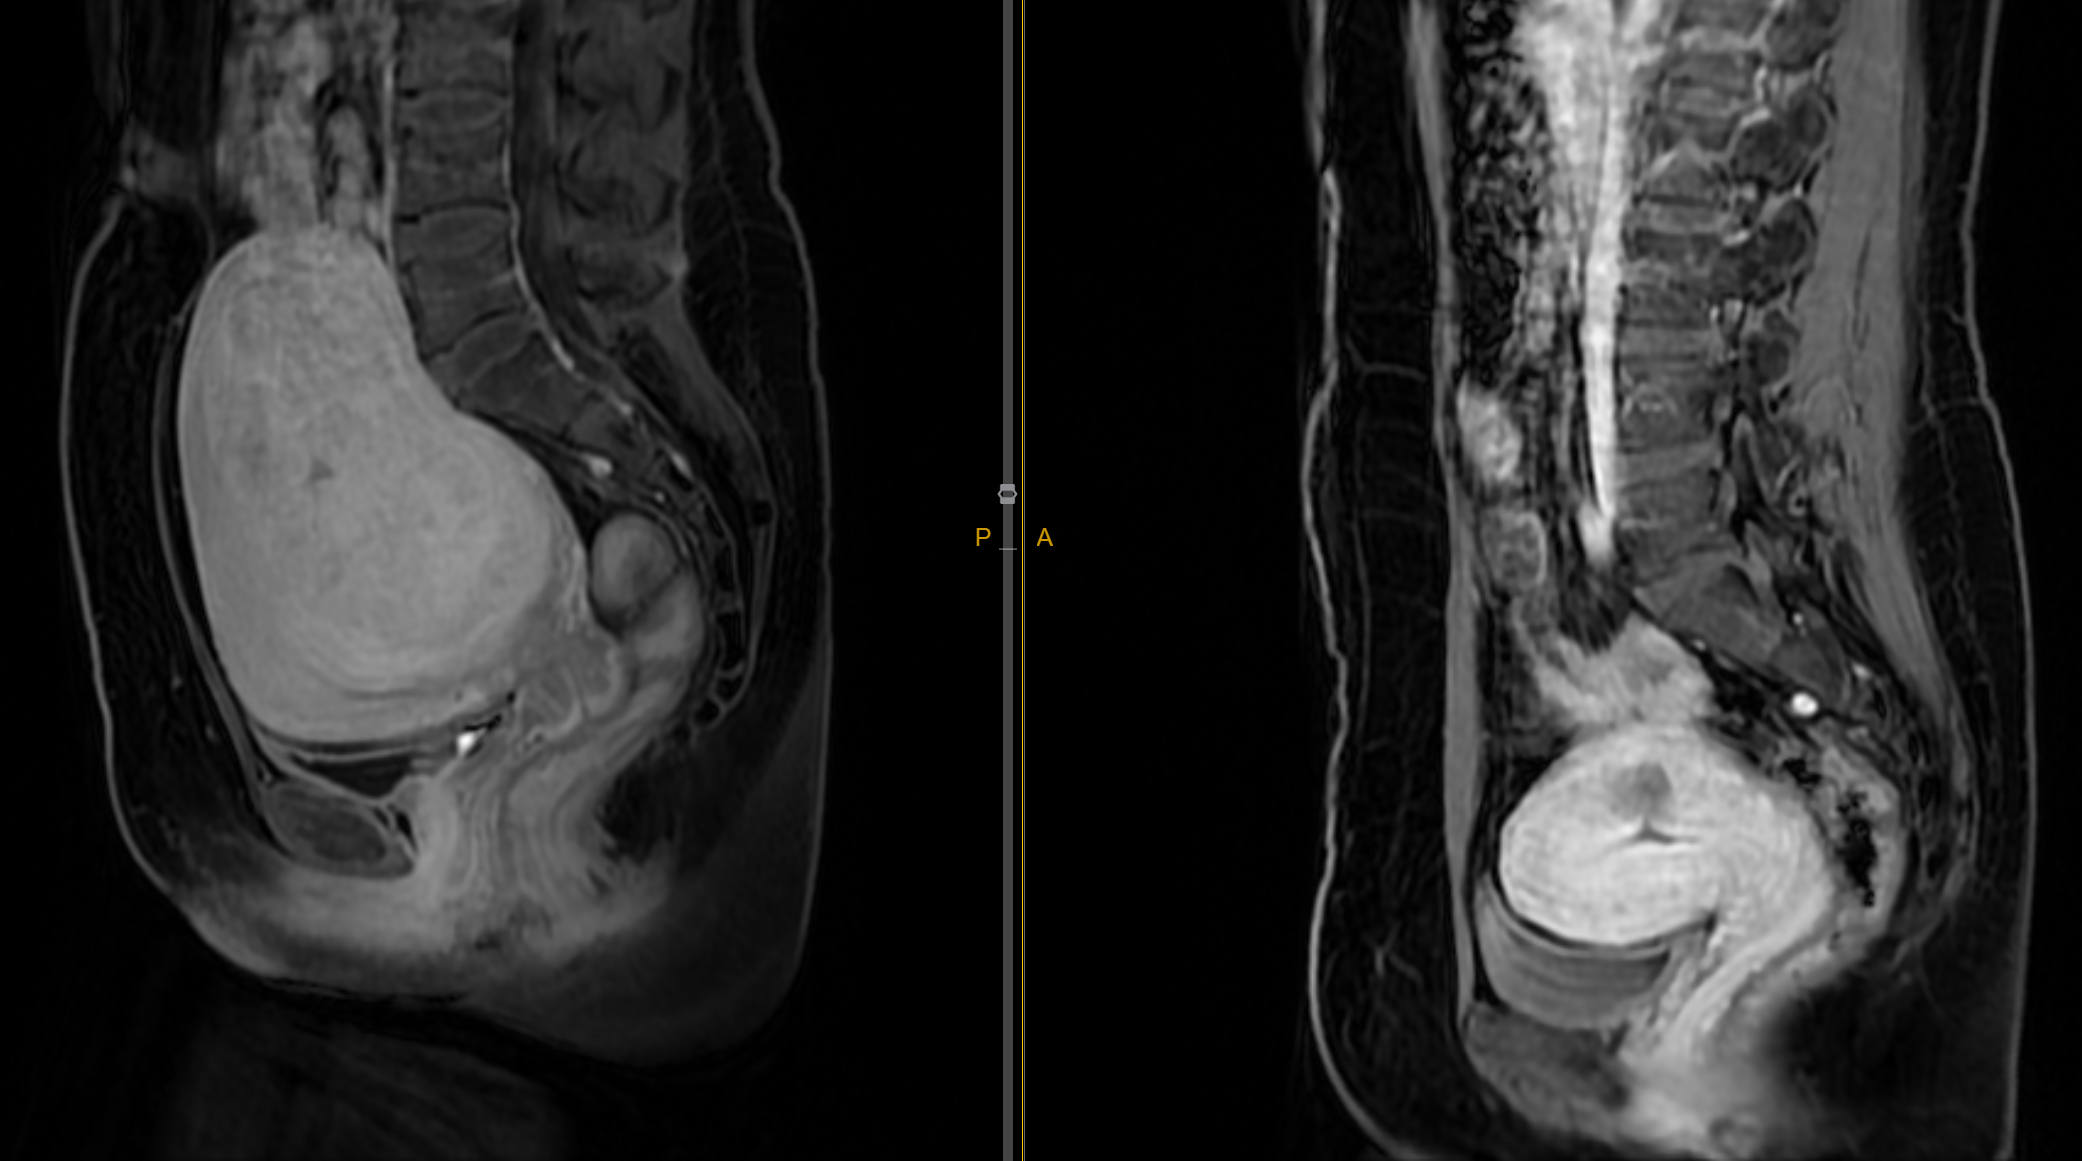

Fibroids can vary greatly in size - from as small as a pea to as large as a melon. Their location within the uterus affects symptoms:

Understanding the blood supply to fibroids is key to UAE treatment. Fibroids receive their blood supply primarily through:

Uterine arteries - the main blood vessels feeding the uterus and fibroids

During UAE, we target these blood vessels to cut off the fibroid's blood supply, causing them to shrink.